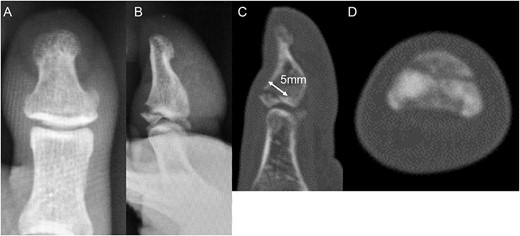

A 54-year-old man injured his right great toe while walking and wearing sandals. He complained of tenderness, swelling, and pain during motion. He could bear weight but could not actively extend the interphalangeal (IP) joint of the hallux. He was referred to our outpatient clinic 3 days after the injury. Physical examination revealed swelling, tenderness, and motion pain, and the patient could not extend the IP joint of the hallux. Plain lateral radiography and computed tomography revealed a displaced avulsion fracture of the dorsal base of the distal phalanx (Fig. 1). Surgery was performed under general anesthesia after informed consent was obtained on posttraumatic day 11. A Y-shaped incision was made at the center of the dorsal IP joint, and the displaced bony fragment was attached to the extensor hallucis longus (EHL). The IP joint was temporarily fixed with a 1.6 mm Kirschner wire, and the fragment was repositioned and fixed with two 1.5 mm cortical screws (APTUS® Hand, Medartis, Basel, Switzerland). A 4-0 FiberWire® (Arthrex, Naples, FL, USA) was fastened as an augmentation proximally to the EHL tendon and distally to the periosteum of the distal phalanx in a figure eight (Fig. 2). Postoperatively, the ankle was externally fixed in dorsiflexion from the leg to the toe, and heel loading was permitted. A total of 4 weeks after surgery, the Kirschner wire was removed to allow active motion of the IP joint of the hallux, and weight bearing was allowed on the hallux 5 weeks postoperatively. Plain radiographs taken 3 months after surgery confirmed bone healing (Fig. 3). A total of 20 months postoperatively, the patient acquired normal function, and the range of motion of the affected IP joint ranged from −3° to 30°, with no difference from the unaffected side (Fig. 4). Skin necrosis or nail deformities were not observed.

Postoperative plain radiographs (A) anterior–posterior view and (B) lateral view show the fragment fixed with two screws and temporarily fixed IP joint with Kirschner wire. Plain radiograph 3 months after surgery (C) anterior–posterior view and (D) lateral view indicates the bone union.